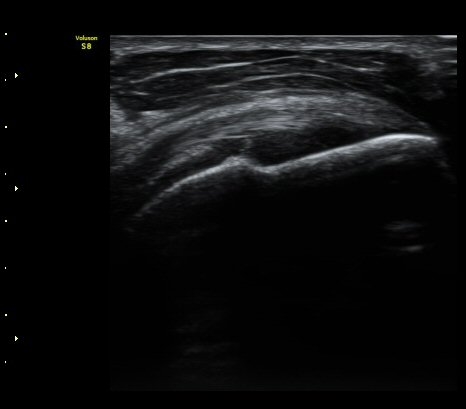

°ß°©ÇÏ±Ù°Ç Á¾´Ü¸é°Ë»ç¿¡¼­ ƯÀÌ ¼Ò°ßÀ» º¸ÀÌÁö ¾ÊÀ½(»çÁø 2, 3)